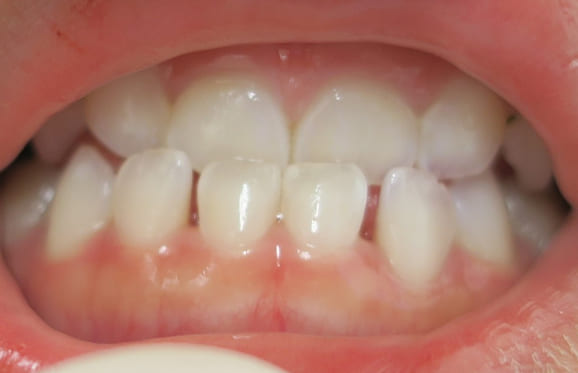

● 咬み合わせ予防

藤沢デンタルオフィスの咬み合わせ予防 藤沢デンタルオフィスの咬み合わせ予防 藤沢デンタルオフィスの咬み合わせ予防

予防矯正装置(i3)を約3か月間使用するだけで反対咬合が治りました。予防矯正装置は、装置をしっかりと使えれば治りますが、年齢的になかなか使いこなすことが難しい装置でもあります。